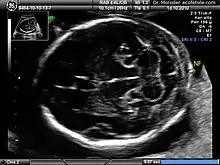

Measurements of fetal nuchal translucency, nasal bone and facial angle according to the standards of the Fetal Medicine Foundation

There are two distinct measurements: the size of the nuchal translucency and the thickness of the nuchal fold. Nuchal translucency size is typically assessed at the end of the first trimester, between 11 weeks 3 days and 13 weeks 6 days of pregnancy.[3] Nuchal fold thickness is measured towards the end of the second trimester. As nuchal translucency size increases, the chances of a chromosomal abnormality and mortality increase; 65% of the largest translucencies (>6.5mm) are due to chromosomal abnormality, while fatality is 19% at this size.[2] A nuchal scan may also help confirm both the accuracy of the pregnancy dates and the fetal viability.

Procedure

Nuchal scan (NT procedure) is performed between 11 and 14 weeks of gestation, because the accuracy is best in this period. The scan is obtained with the fetus in sagittal section and a neutral position of the fetal head (neither hyperflexed nor extended, either of which can influence the nuchal translucency thickness). The fetal image is enlarged to fill 75% of the screen, and the maximum thickness is measured, from leading edge to leading edge. It is important to distinguish the nuchal lucency from the underlying amniotic membrane.[8]

Normal thickness depends on the crown-rump length (CRL) of the fetus. Among those fetuses whose nuchal translucency exceeds the normal values, there is a relatively high risk of significant abnormality.